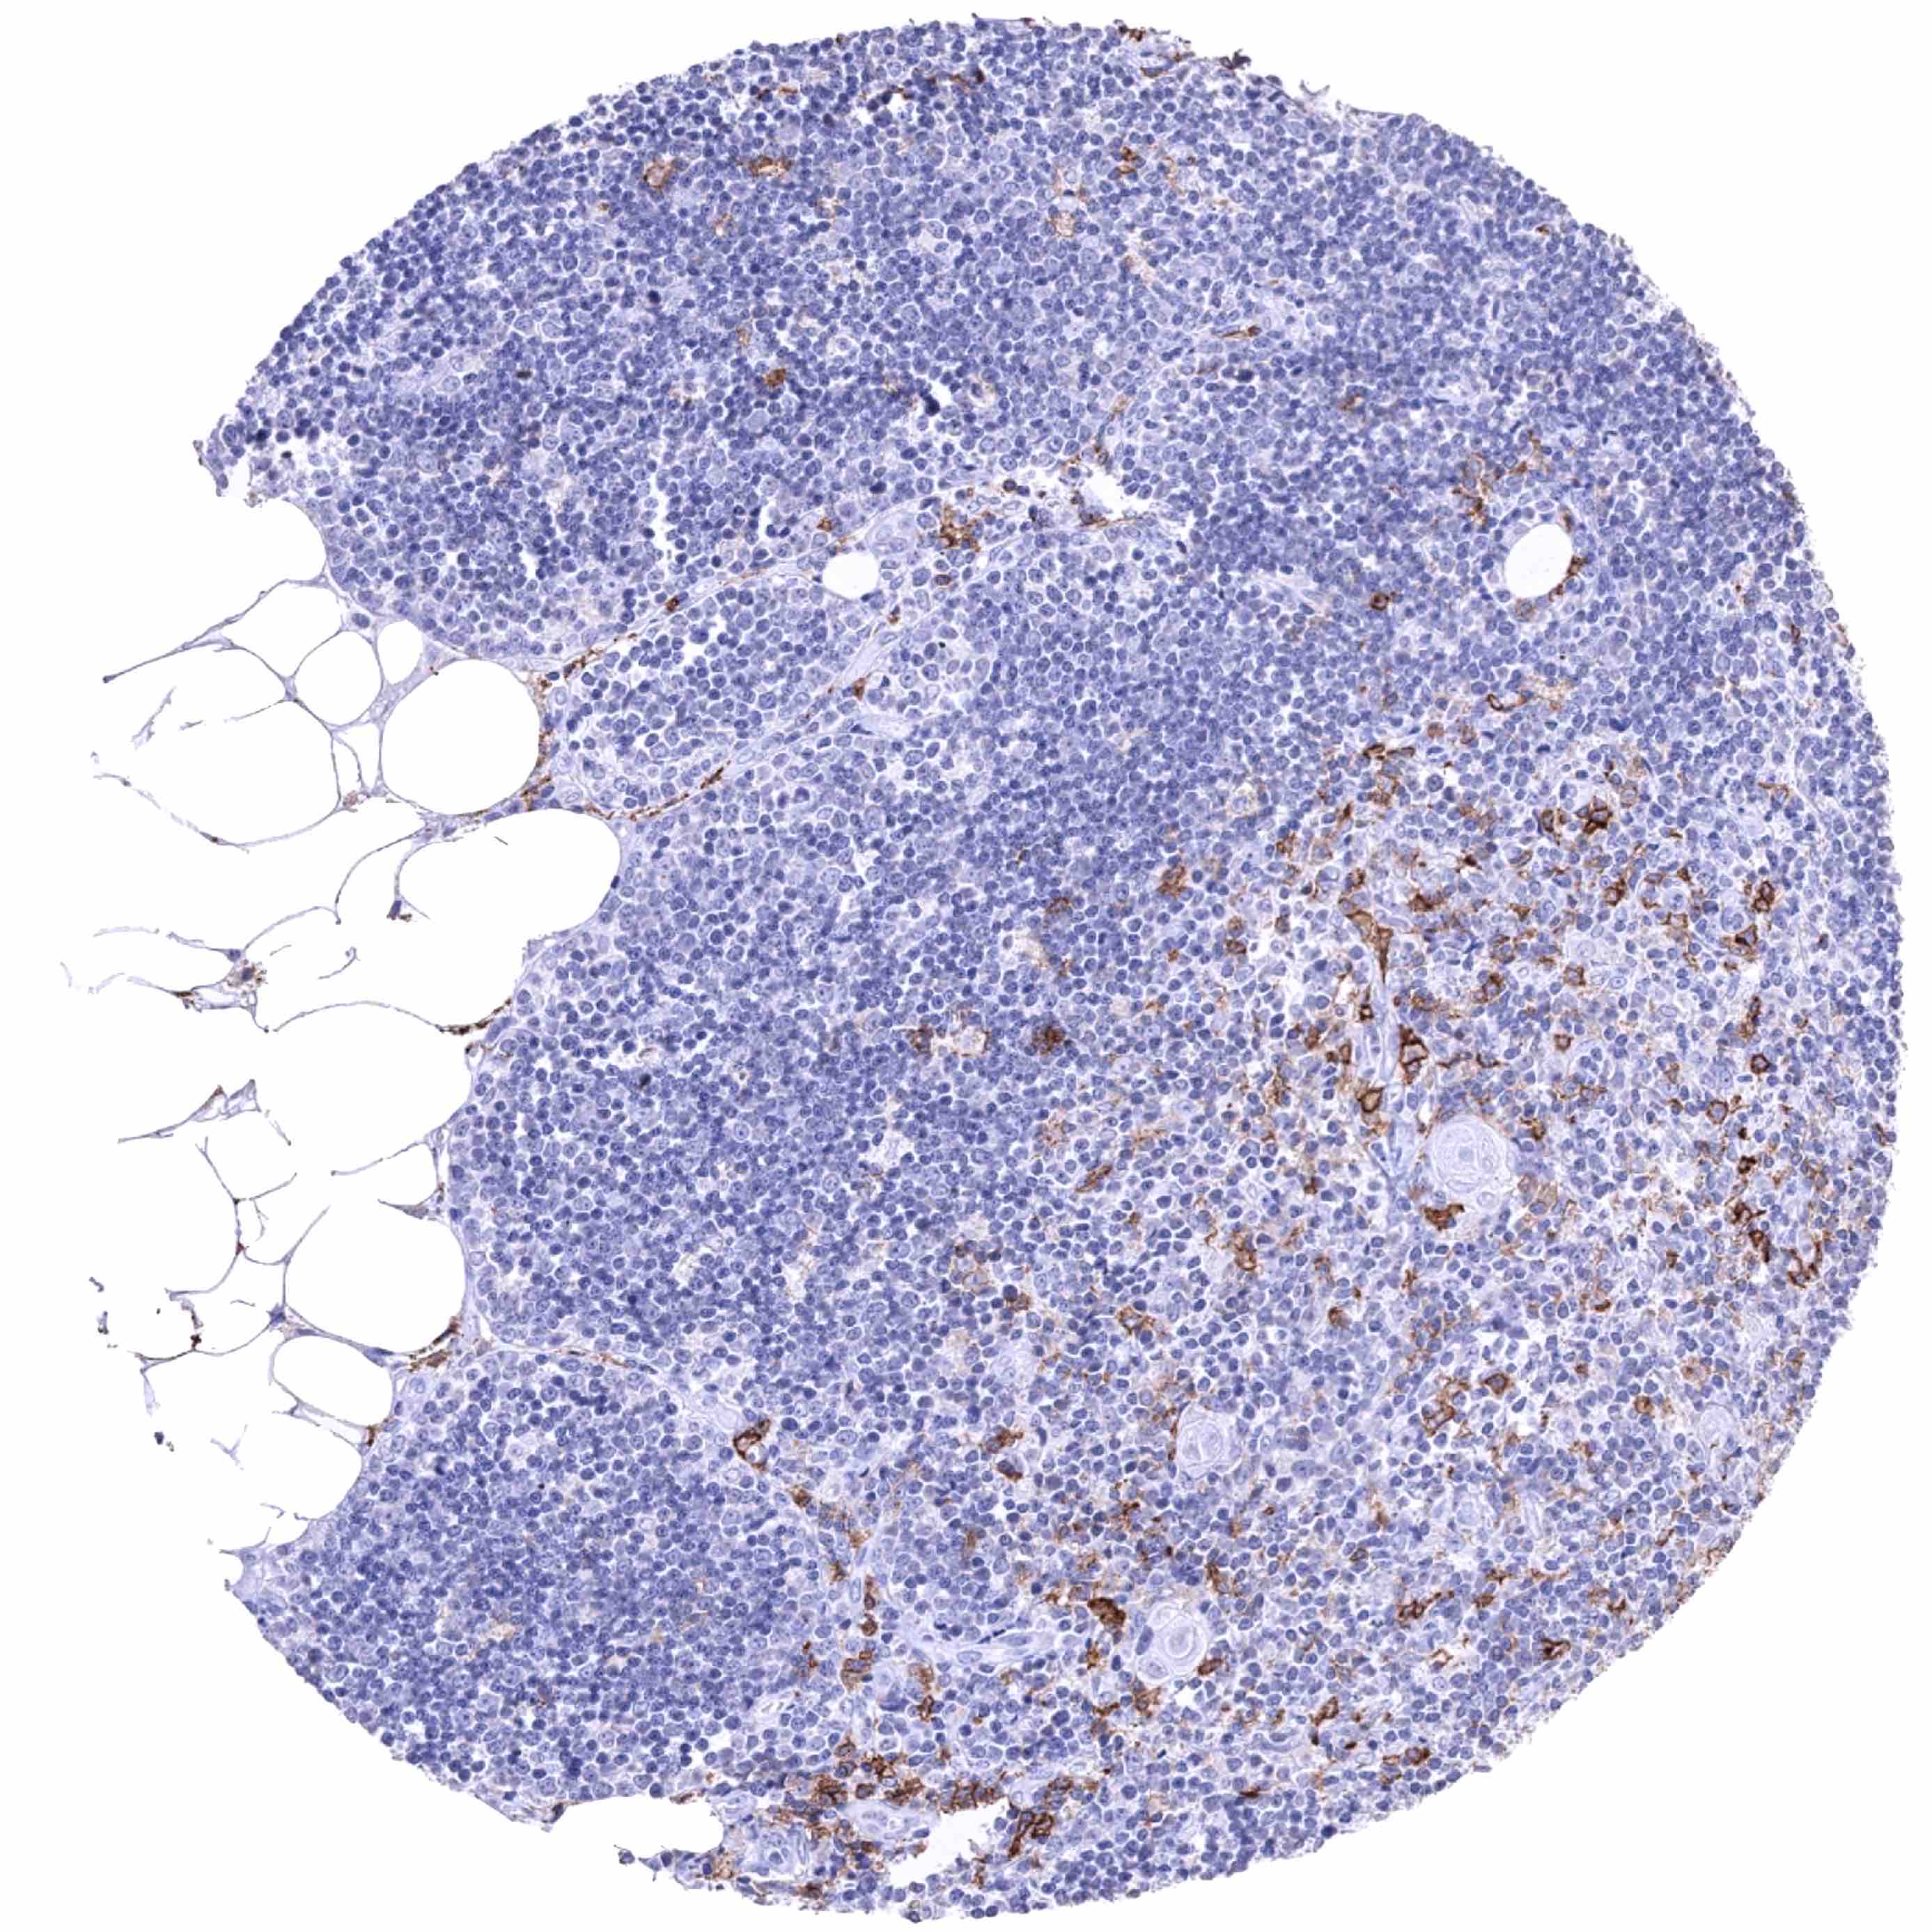

Lymph node – CD38B staining of variable intensity in a large fraction of B-lymphocytes and perhaps also other cells